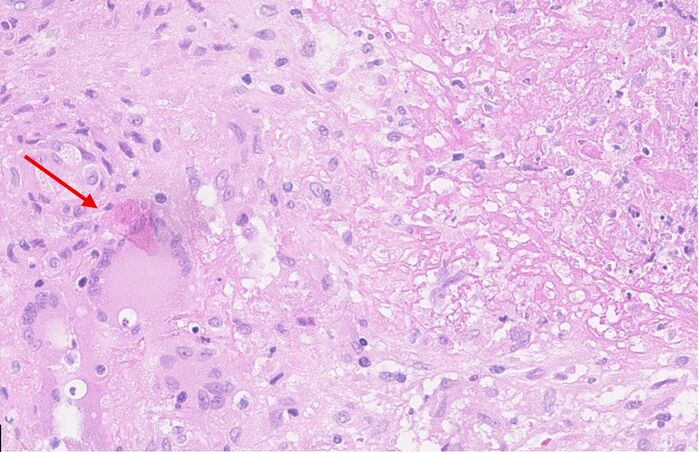

Mynd 2. Tölvusneiðmynd af lungum hjá sjúklingi sem sýnir íferðarfláka ofan til í báðum lungum með holumyndun (cavitation) (rauð ör).

TS af lungum sýndi umtalsverðar breytingar í efri lungnablöðum, en þar sáust nokkrir íferðarflákar í báðum lungum ásamt byrjandi holumyndun (Mynd 2). TS af kviðarholi var án athugasemda. Berklar voru taldir vera líklegasta greiningin út frá þessum rannsóknum þrátt fyrir lítil einkenni. Í framhaldinu var ráðlagt að fá þrjú hrákasýni og senda í litun fyrir sýruföstum stöfum og í berklaræktun. Einnig var sent blóðsýni í HIV-rannsókn og IGRA-próf (interferon gamma release assay) (Quantiferon®).